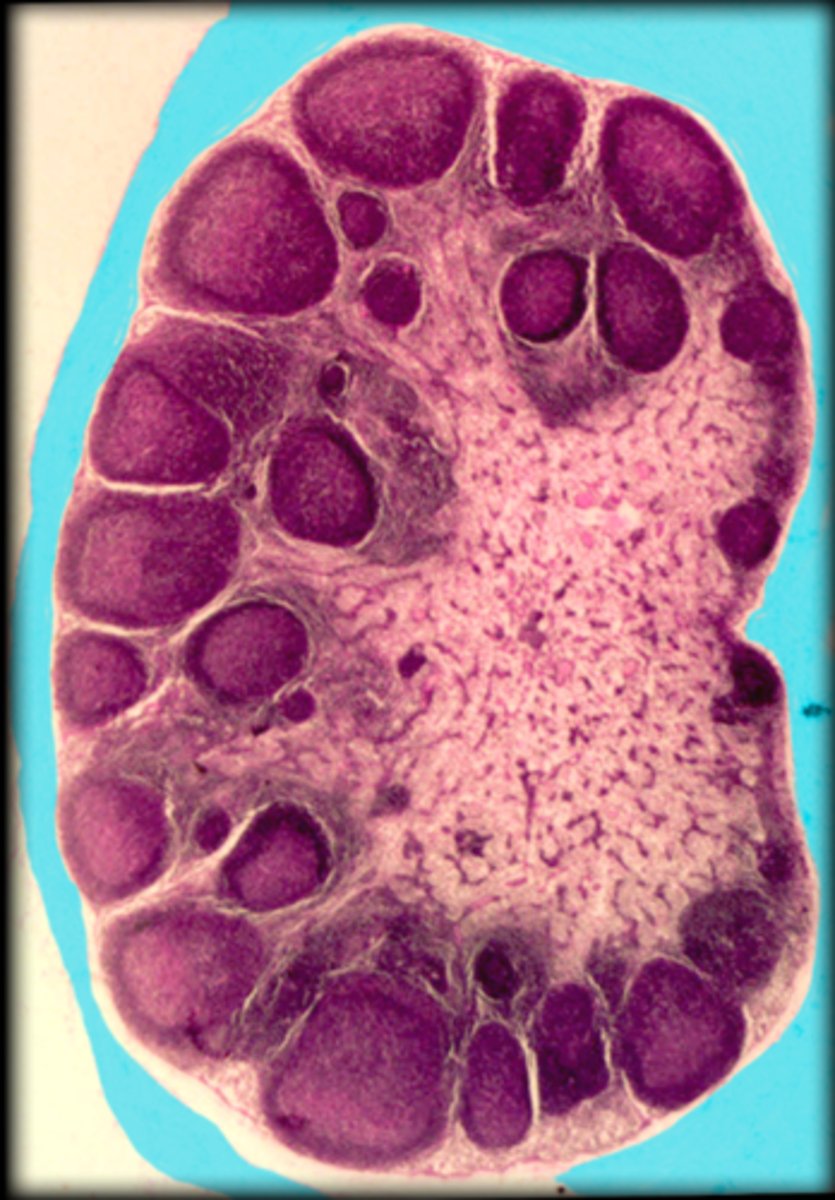

capsule

Lymph node

cortex

medullary cord

medullary sinus